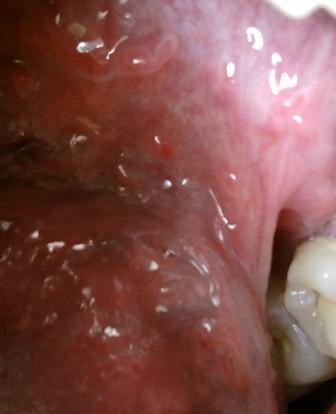

石家庄治疗尖锐湿疣选择哪家医院虽然尖锐湿疣比较难以治愈,但是在性传播疾病中只要治疗得当,持续治疗,是可以达到临床治愈目的的。尖锐湿疣是一种性病,主要发病部位是人们的生殖器官周围,而且现在这种疾病的发病率是比较高的。